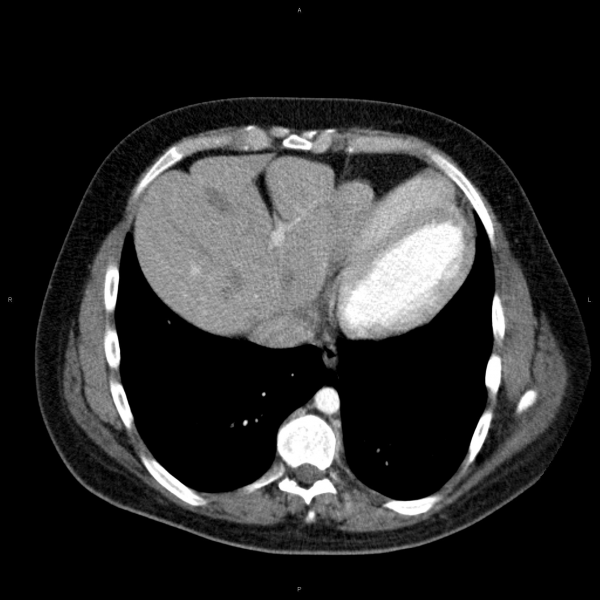

Анатомия диафрагмы и треугольника Бохдалека

Раздел: Визуальный дайджест